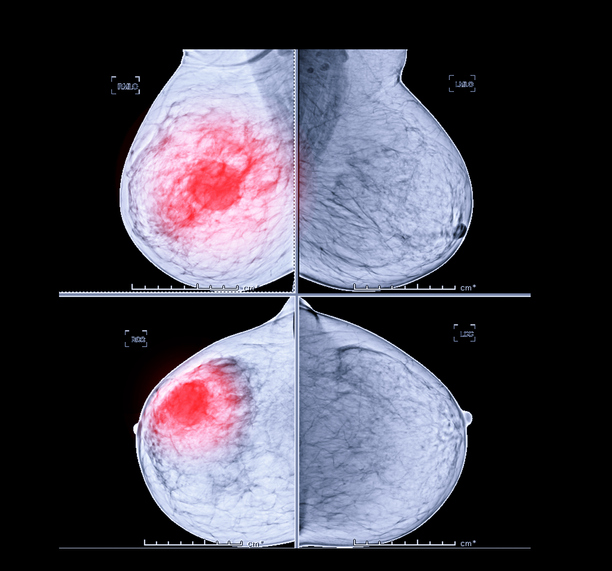

유방에 있는 2cm 길이의 덩어리를 결절이라고 하고 이 크기보다 큰 것을 덩어리라고 합니다. 덩어리는 가장 흔한 증상으로 유방암 증상의 약 70%를 차지합니다. 흔히 유방 덩어리를 만질 때 통증이 없다고 생각하는데 이는 잘못된 것입니다. 대부분의 덩어리는 통증이 없으므로 젊은 여성이 자가 검진을 통해 덩어리를 느끼면 암이라고 생각하고 병원에 가는 것이 좋습니다. 20대의 경우 유방암 발병률은 2.2%입니다.

유방암 자가진단법

유방암 자가진단 방법은 유방을 만져서 덩어리가 있는지 확인하는 것이다. 이 경우 위쪽 가슴을 시계 방향으로 누르면서 덩어리를 느낄 수 있습니다. 가슴이 크면 등을 대고 누운 상태에서 가슴 바깥쪽을 만져보면 덩어리를 찾을 수 있습니다. 또 다른 방법은 거울 앞에서 모양을 보고 머리 뒤로 손을 대고 가슴 모양과 주름, 피부 보조개를 관찰하는 것입니다. 이상한 모양이 관찰되면 해당 부위 주변에 만져지는 덩어리가 있는지 확인하십시오.